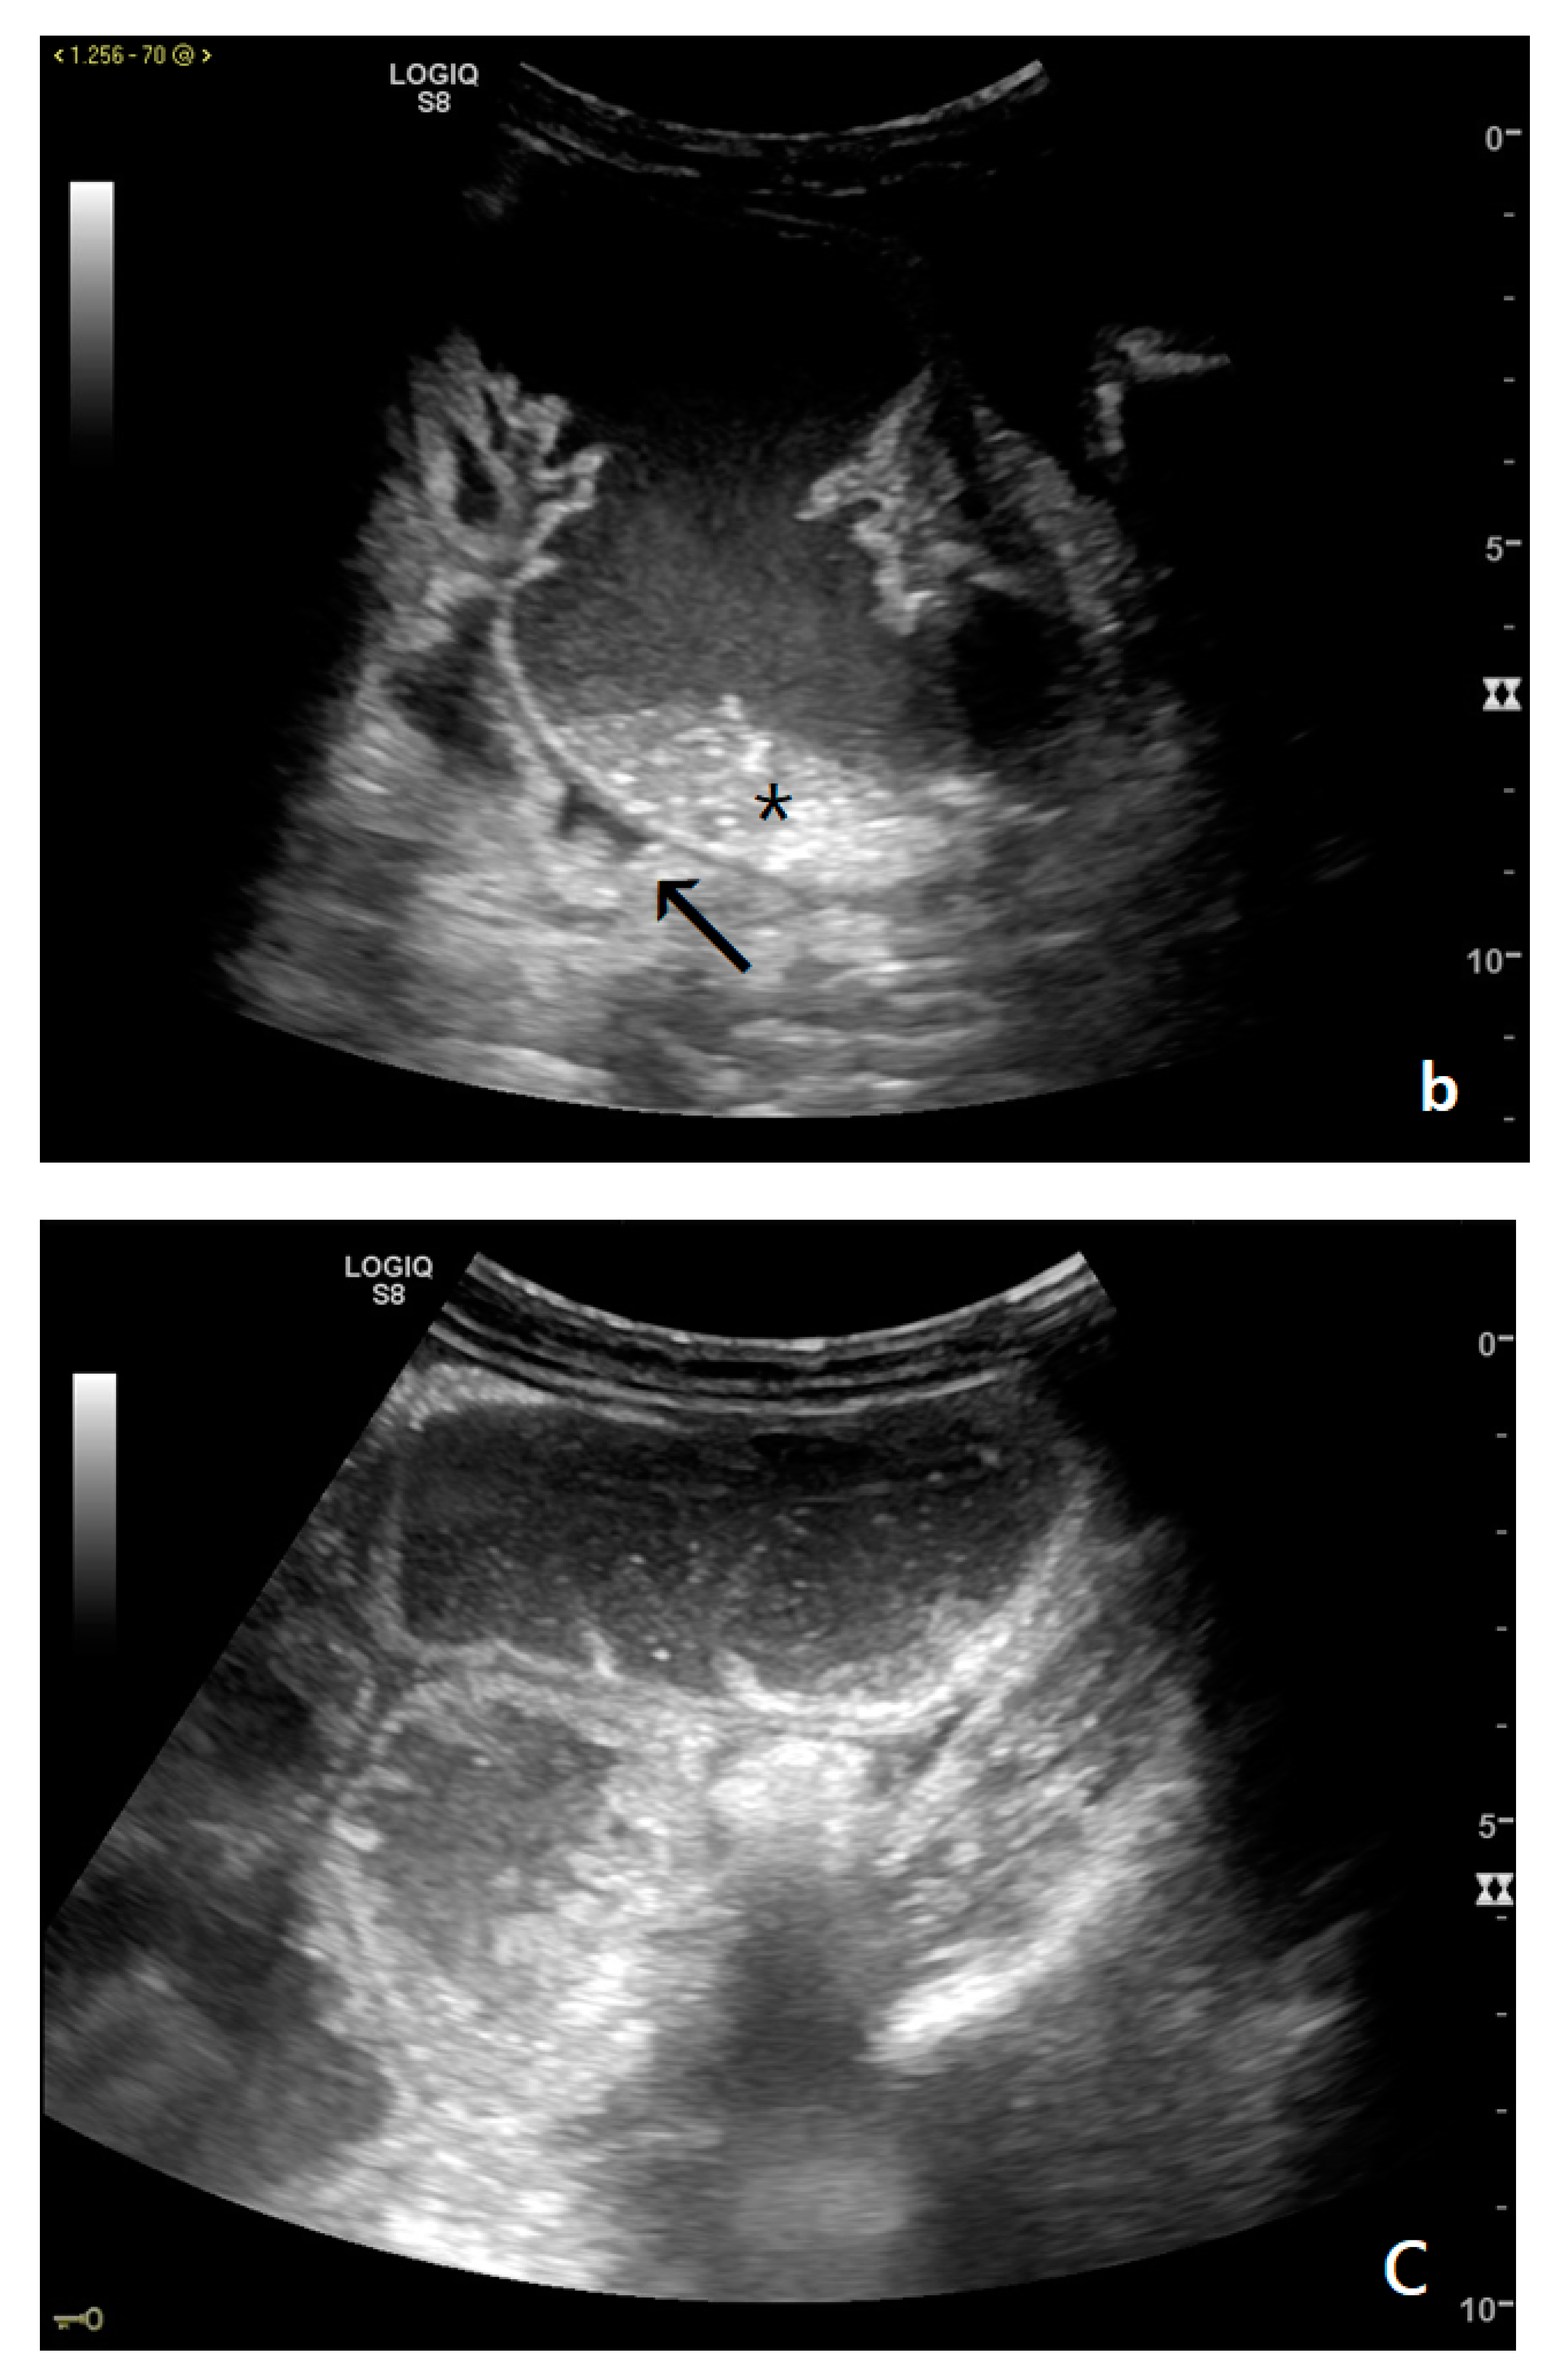

Figure 3.

A decompensated SBO, presenting fluid-filled, dilated small bowel loops with increased parietal thickening (*) (a) and free fluid between bowel loops (a). ‘Caliber jump’: a difference in caliber between the swollen loops upstream (white arrows) (a,b) and the collapsed loops downstream of the obstruction (black arrows) (a,b).

3.2.1. Free Fluid

The persistence of obstruction causes an increase in endoluminal pressure, and the liquid content normally present in the intestinal lumen cannot be reabsorbed. Bowel layers act as a sponge, determining the passage of fluid in the peritoneal cavity (Figure 3a,b). In the initial phase, the liquid is disposed between the recesses of the mesenteric fan, giving rise to the characteristic ‘sign of the thong’ [39]. With the persistence of the obstruction, the amount of free fluid increases, and it can be found in the abdominal cavity. The presence of free fluid is directly correlated to bowel parietal vascular alterations [13,37,40,41].

These refer to the ‘bowel loop jump’—the visualization of two groups of loops with a clear difference in size (‘caliber jump’) or peristalsis (‘kinesis jump’). In both cases, a comparison should be made between the loop upstream and that downstream of the obstruction [12].